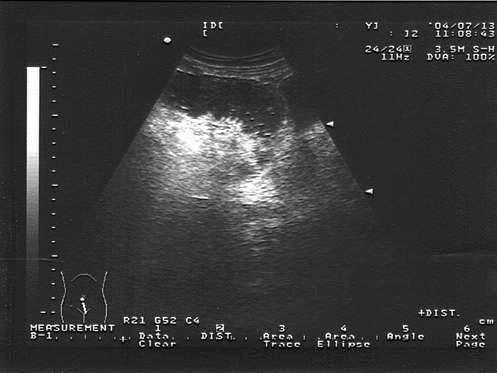

问题 女,51岁,肛门停止排便排气1天。腹痛、无呕吐,有乙状结肠手术史。结合超声声像图,诊断为?(?)

选项 A.肠梗阻 B.输卵管积液 C.肠套叠 D.盆腔积液 E.结肠癌

答案 A